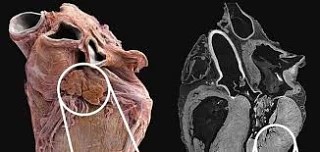

КАК ВЫЖИТЬ ПРИ СЕРДЕЧНОМ ПРИСТУПЕ, КОГДА ВЫ ОДИН? Поскольку многие люди находятся одни в момент, когда случается сердечный приступ, перед тем как человек потеряет сознание, у него есть всего около 10 секунд, после того как его сердце начинает биться неравномерно и он начинает чувствовать что сейчас потеряет сознание.

Однако такие жертвы могут помочь себе многократным и очень энергичным кашлем. Перед каждым кашлем нужно сделать глубокий вдох. Кашель должен быть глубоким и продолжительным как при отхаркивание мокроты из глубины легких. Вдох и кашель должны повторяться примерно каждые 2 секунды без перерывов пока не подоспеет помощь или пока не почувствуете что сердце опять начало биться нормально.

Глубокие вдохи поставляют кислород в легкие, а кашляющие движения сжимают сердце и поддерживают циркуляцию крови. Сжимающее давление на сердце так же помогает ему восстановить нормальный ритм. Таким образом, жертвы сердечного приступа могут добраться до больницы.